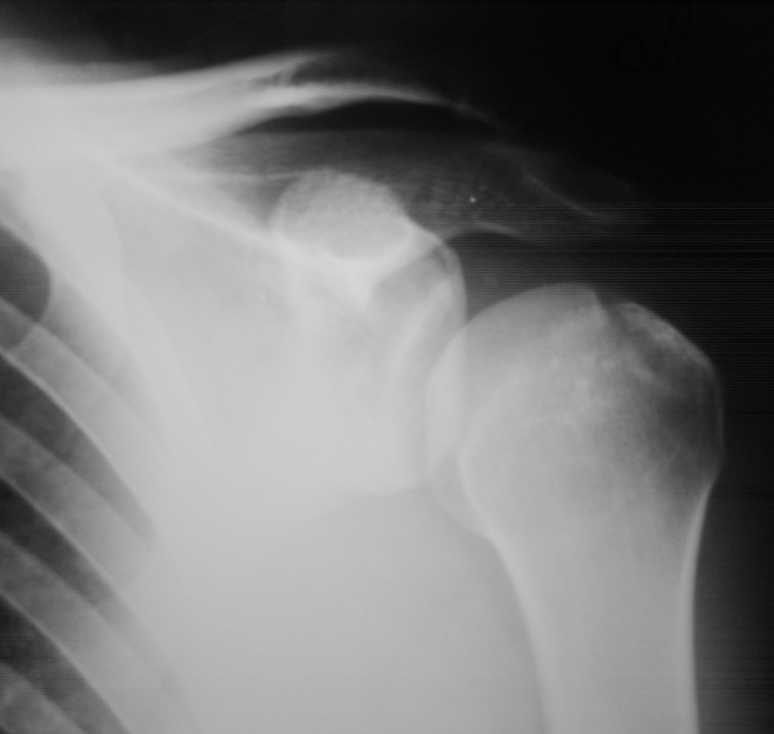

Множественные травмы скелета.(застарелый разрыв левого АКС)

Падение на очередной гонке. По рассказу пациента произошел вывих плеча, который доблестные мед. работники города Саранска вправили "наживую" прямо на стадионе. Больного не фиксировали. По приезду зафиксировали плечо в наружной ротации (см. фото). Сделали Кт (На серии КТ с толщиной срезов 3 мм в левой плечевой кости определяется отрыв большого бугорка, определяется линейный перелом клювовидного отростка левой лопатки без смещения отломков (стрелки). В полости сустава- небольшое количество жидкости. В головке плечевой кости определяется эностоз. Определяется краевые костные разрастания акромиального конца ключицы.Заключение: перелом левой лопатки и плечевой кости.)Возникли вопросы по дальнейшей фиксации: Стоит ли давать отведение?Ну и дальнейшая тактика ведения больного.Спасибо за внимание.

В этом случае консервативная терапия наиболее оптимальный метод лечения. Судя по снимку перелом большого бугорка без смещения.Отведение не обязательно. Через 3 недели приступить к разработке движений в суставе. Прогноз благоприятный.